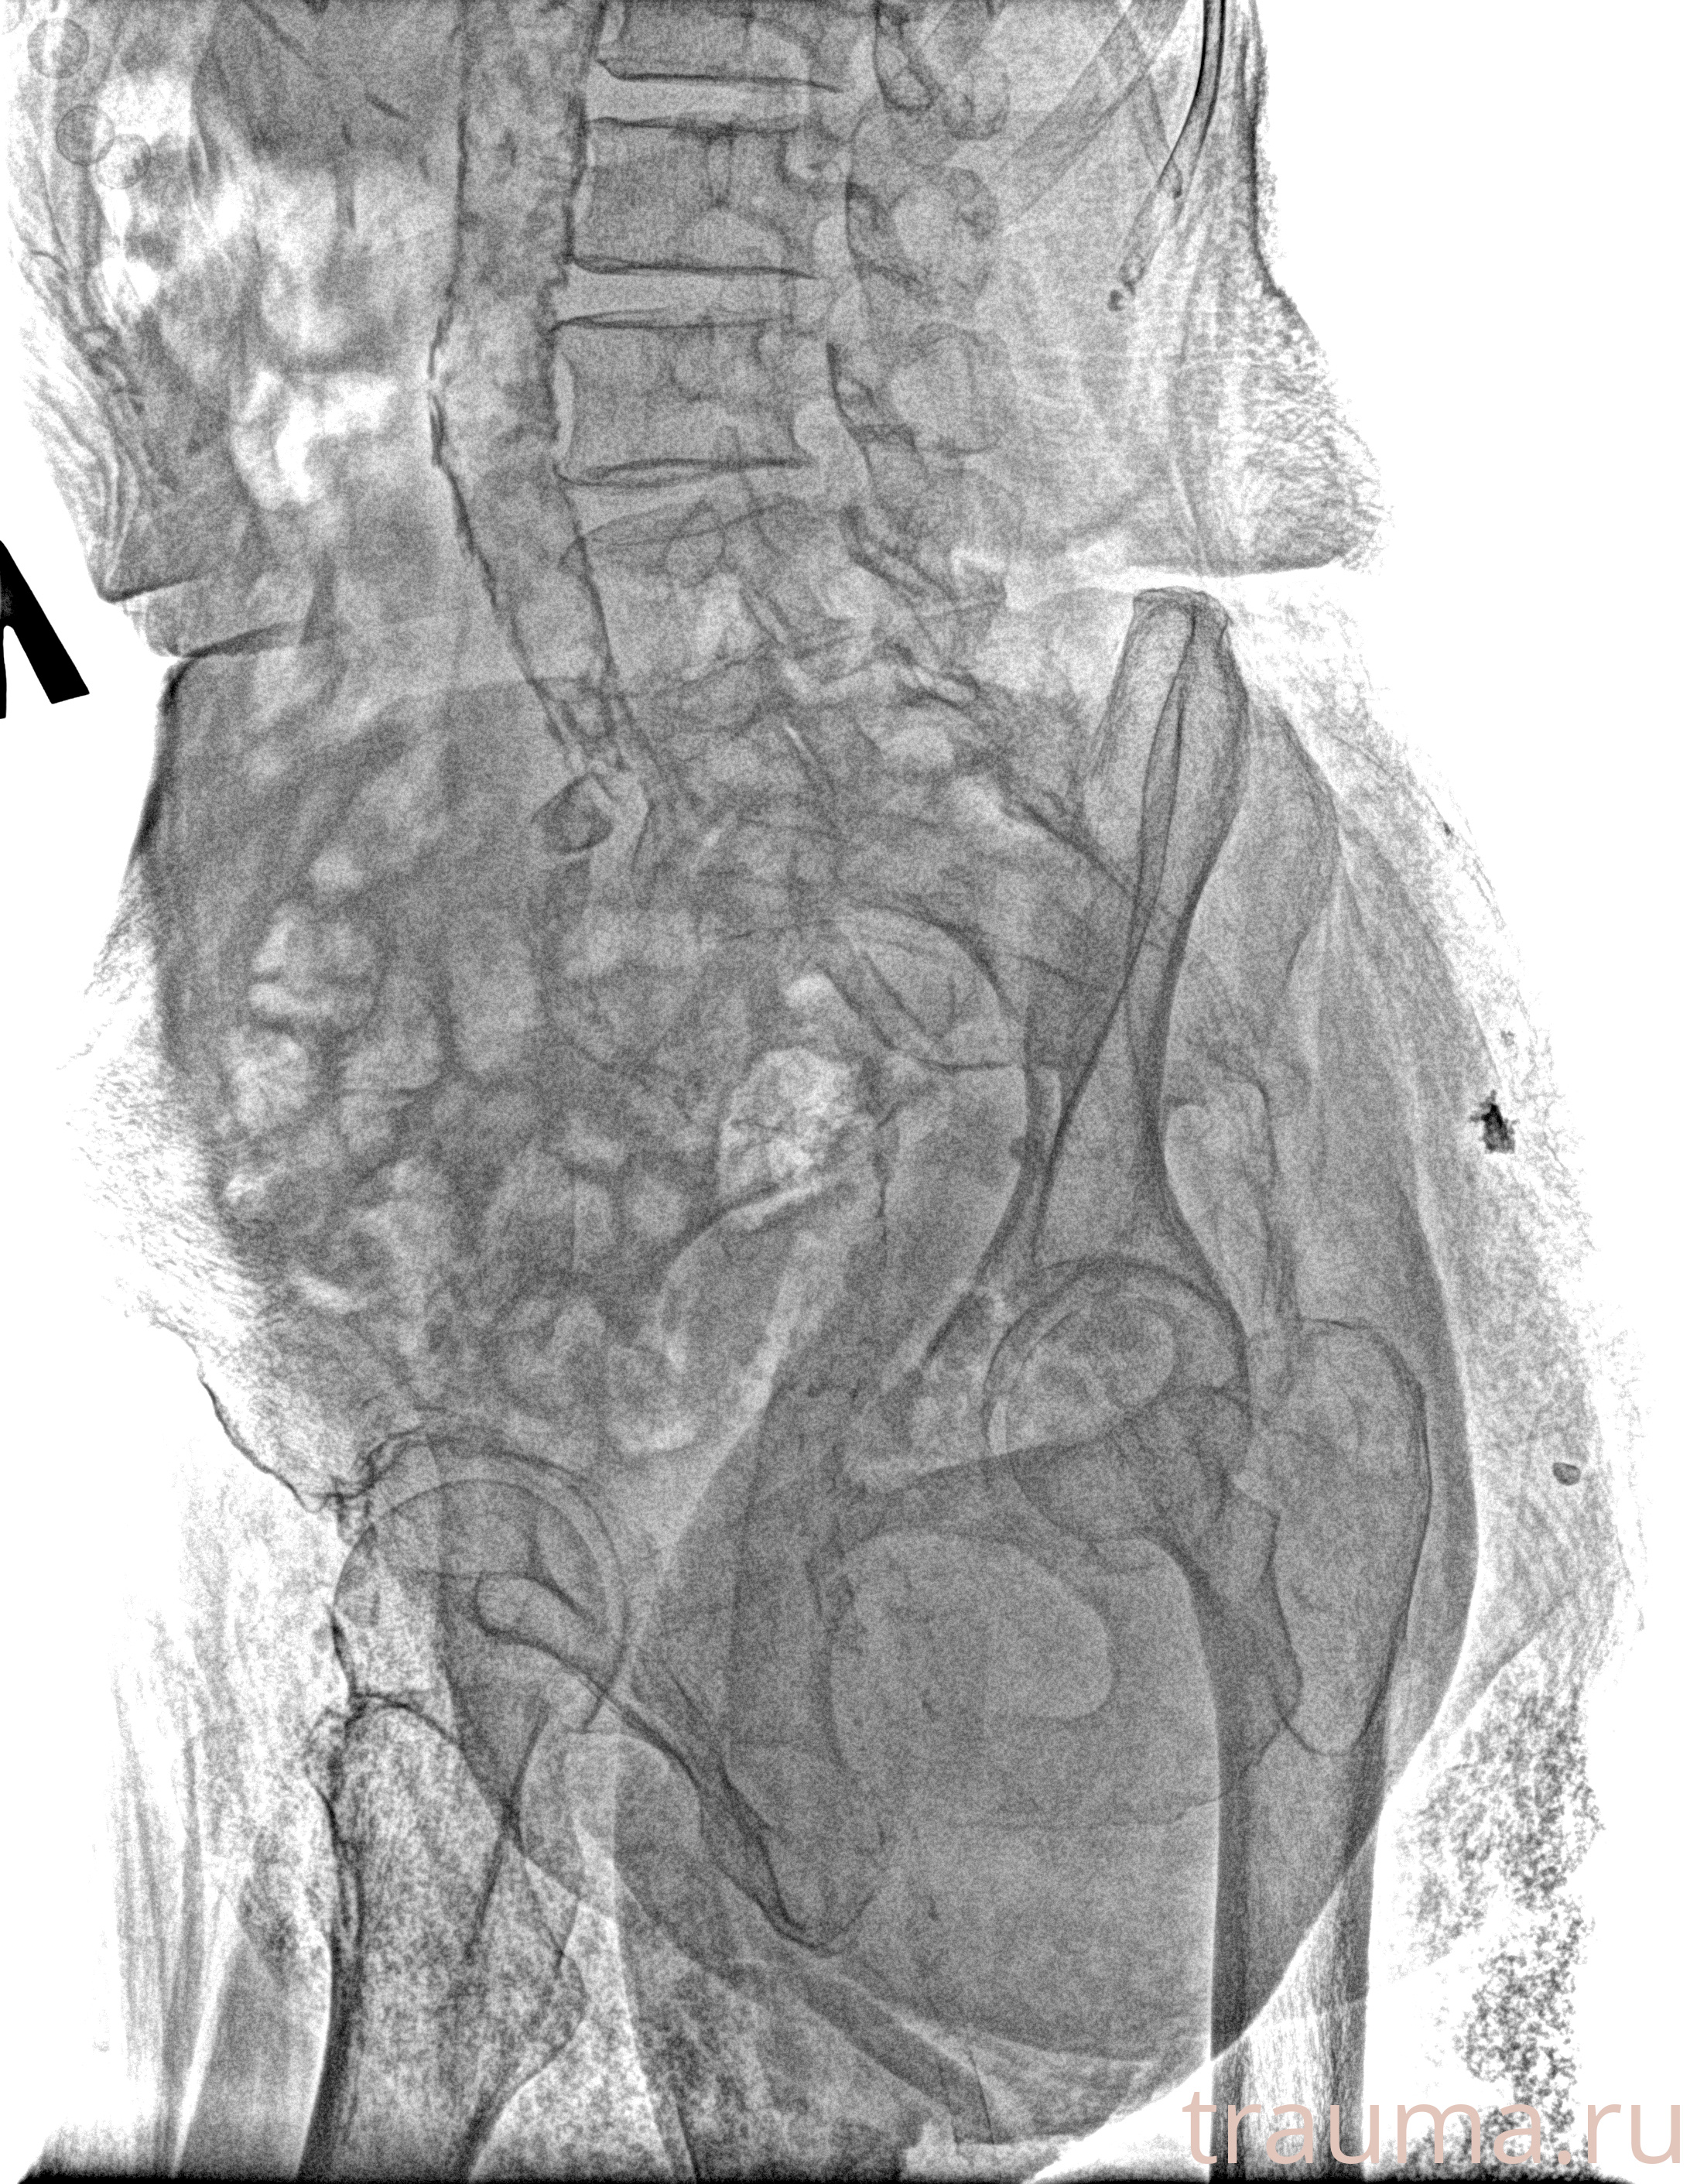

Рентгенограммы

Рентген на дому: по вашему адресу приезжает врач-рентгенолог, травматолог-ортопед с мобильным рентгеновским аппаратом, проводит диагностику травмы или заболевания, делает необходимые рентгенограммы, дает рекомендации по дальнейшему лечению. Получить качественные снимки в домашних условиях возможно благодаря уникальной методике, разработанной МосРентген Центром для института  Склифосовского